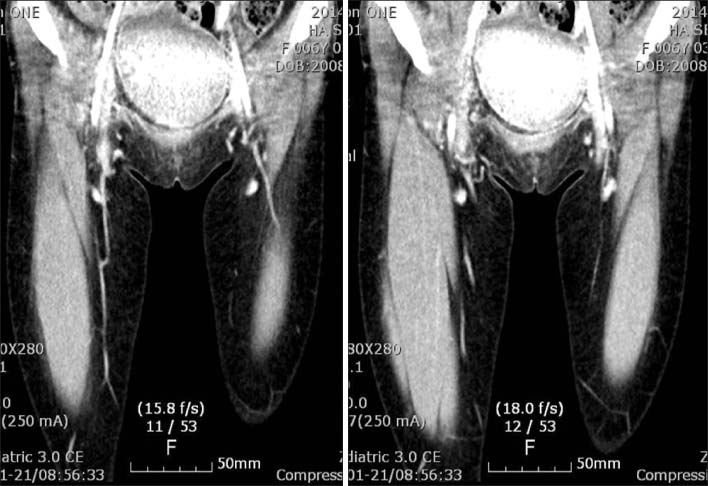

Fig. 1

Ultrasonography showed abnormal echogenic fatty mass in the right inguinal fossa (3×1.3×4.3 cm) with minimal movement during Valsalvar's maneuver.

Fig. 1 Ultrasonography showed abnormal echogenic fatty mass in the right inguinal fossa (3×1.3×4.3 cm) with minimal movement during Valsalvar's maneuver.